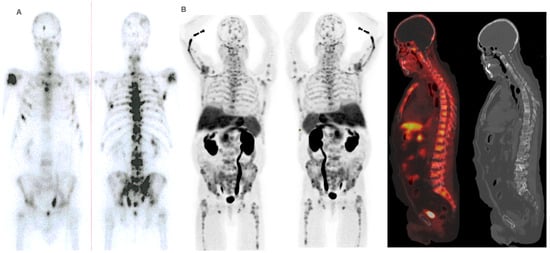

Performance status before 223Ra (p < 0.001), AP baseline levels (p < 0.001), and LDH (p = 0.033) were found to have a significant impact on OS (Figure 1), as well as other factors such as completion of treatment with 223Ra (p < 0.001). Regarding imaging variables, both the chi-square and the log-rank tests showed that derived FCH PET/CT variables had statistical significance. Thus, high tumor burden (p = 0.003), uptake of the most hypermetabolic lesion above the liver (p < 0.001), or STI in the FCH PET/CT study (p = 0.048) were associated with a lower median OS (Figure 2). Focusing on treatment response assessment, only interim studies (BS and FCH PET/CT) showed a significant association with OS, with data extracted from FCH PET/CT being slightly more robust compared to BS (p < 0.001 vs. p = 0.004, respectively) (Figure 3). The significant variables in the univariate analysis were included in the multivariate analysis for the OS and therapeutic failure end-points. In the former, the association of uptake of BM above the liver (p = 0.011), therapeutic failure (p = 0.001), or pathological baseline AP (p = 0.011) was highlighted as leading to lower OS. Table 8 details the results of the univariate Cox regression, and Table 9, Table 10 and Table 11 show the results of the log-rank test regarding OS.

PET/CT-derived functional parameters, such as maximum and mean SUV and lean body mass corrected SUV peak (SUL peak), have been investigated as potential biomarkers for patients’ prognostication before therapy. Previous works using baseline FCH PET/CT have shown controversial results, with no associations of SUVmax with response to treatment [39,40,41,42] and a negative correlation of SUVmax with PFS and OS in patients receiving enzalutamide [43,44]. Furthermore, volumetric SUV-based parameters, namely metabolically active tumor volume (MATV) and total lesion activity (TLA), both reflecting the burden of metabolically active disease, were found to have a significant prognostic impact [42,44,45,46]. In addition, FCH PET may be useful for patients’ stratification before 223Ra therapy, with high MATV the only reported significant predictor of OS (p = 0.003; HR = 7.6) in multivariate Cox analysis [42]. In the current study, both the SUVmax value of the lesion with the highest uptake and the average SUVmax of the five lesions with the highest uptake were evaluated in the FCH PET/CT studies, showing both a significant association with OS. Additionally, perhaps a more robust or comparable among works variable, such as the existence of at least a lesion with uptake higher than the liver, proved to be another independent variable associated with OS (Figure 5 and Figure 6).

Given the similar uptake properties of 223Ra and BS tracer in osteoblastic bone, a reasonable hypothesis is that metastatic disease with higher uptake on BS or 18F-NaF PET/CT compared to FCH PET/CT, is more likely to respond to 223Ra therapy, based on that increased choline levels can reflect on more aggressive tumors [39,40,41,42,43,44,47,48]. Ahmadzadehfar et al. [49] reported that when PSMA PET/CT is used as the gatekeeper in addition to BS, radionuclide therapy with 223Ra might be more effective and have more success regarding changes in the PSA, mainly because of better patient selection with the exclusion of patients with bone marrow involvement or STI. In our case, similar results were found with the combined use of FCH PET/CT and BS, as some of the FCH PET/CT variables had significant associations with OS. These included bone marrow infiltration (median 6 vs. 14 months; p < 0.001), uptake of the most hypermetabolic BM above the liver (median 10.5 vs. 16 months; p < 0.001), and STI (median 7 vs. 14 months; p = 0.048).

Figure 5. Patient ≠ 1. A 71-year-old man, diagnosed with prostate adenocarcinoma Gleason Score 9 (4 + 5), underwent prostatectomy followed by adjuvant radiotherapy to the surgical bed due to early PSA progression. Three years after diagnosis, bone metastases were detected, prompting the start of systemic treatment lines (Enzalutamide and Docetaxel). 223Ra was administered as the third line. At the start of treatment, the patient was in good general condition (ECOG 0), experienced pain, and had baseline PSA levels of 50.7 ng/dL, AP of 377 IU/L, and LDH of 377 IU/L. Baseline BS (A) shows polymetastatic disease (>20 lesions) affecting both the axial and extra-axial skeleton. Baseline FCH PET/CT (B) shows the presence of mixed characteristic BM, bone marrow infiltration, and uptake of the most hypermetabolic BM higher than liver and soft tissue involvement at the pelvic lymph nodes. The concordance between both studies was moderate, defining FCH PET/CT more BM with respect to BS.

Cancers 16 02695 g005

Figure 6. Patient ≠ 1. PSA and AP showed a steady increase after 223Ra initiation. Clinical deterioration was observed after the third 223Ra administration. Interim BS (A) and FCH PET/CT (B) show disease progression. The patient died 6 months after starting treatment with 223Ra.